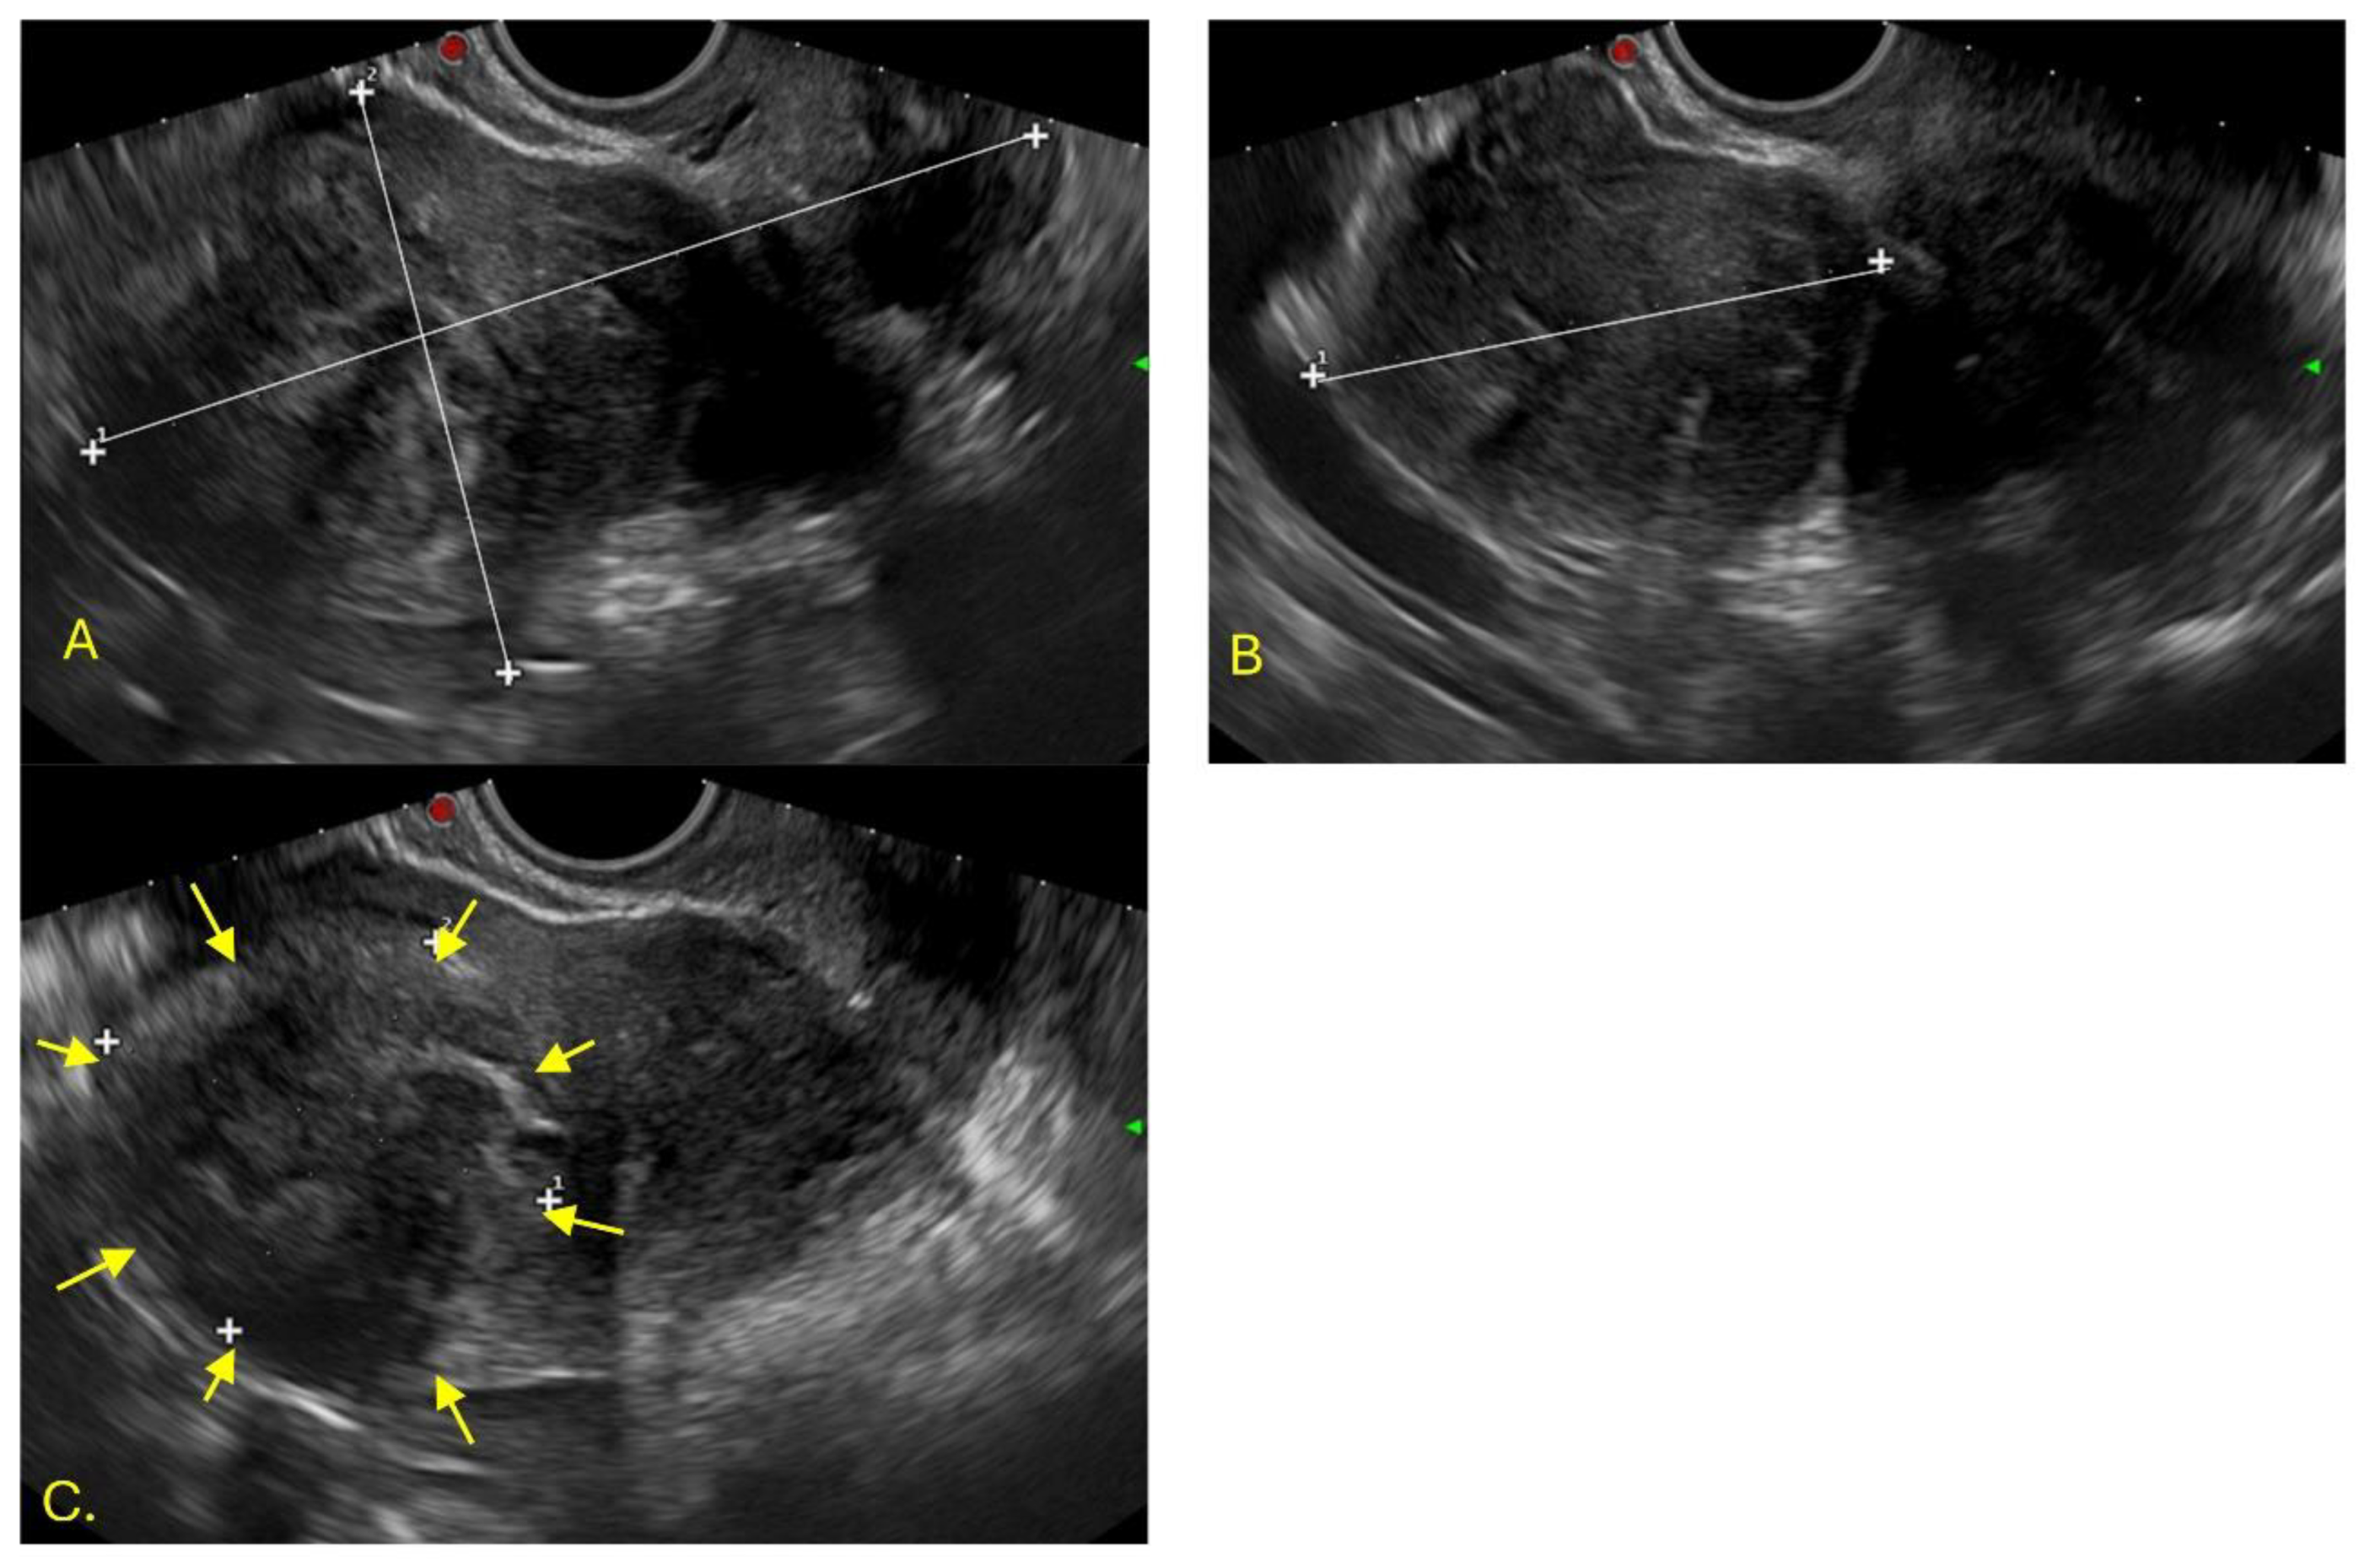

An endovaginal ultrasound was performed in the imaging department, identifying two uteri. The left uterus, with lobulated borders, measured 105x90x90mm and showed a heterogeneous myometrium, with two solid nodular images: one intramural, 50x48mm, and the other posterior, 36x43mm, corresponding to FIGO 2 and 3 fibroids (Figure 1).

Figure 1. Endovaginal ultrasound of the right cavity. Image A) Sagittal plane of the left uterus: length 105 mm, anteroposterior diameter 90 mm. Image B) Transverse diameter 90 mm. Image C) Heterogeneous myometrium with a solid nodular image measuring 50 x 48 mm intramurally. Image D) Posterior myoma measuring 36 x 35 mm.